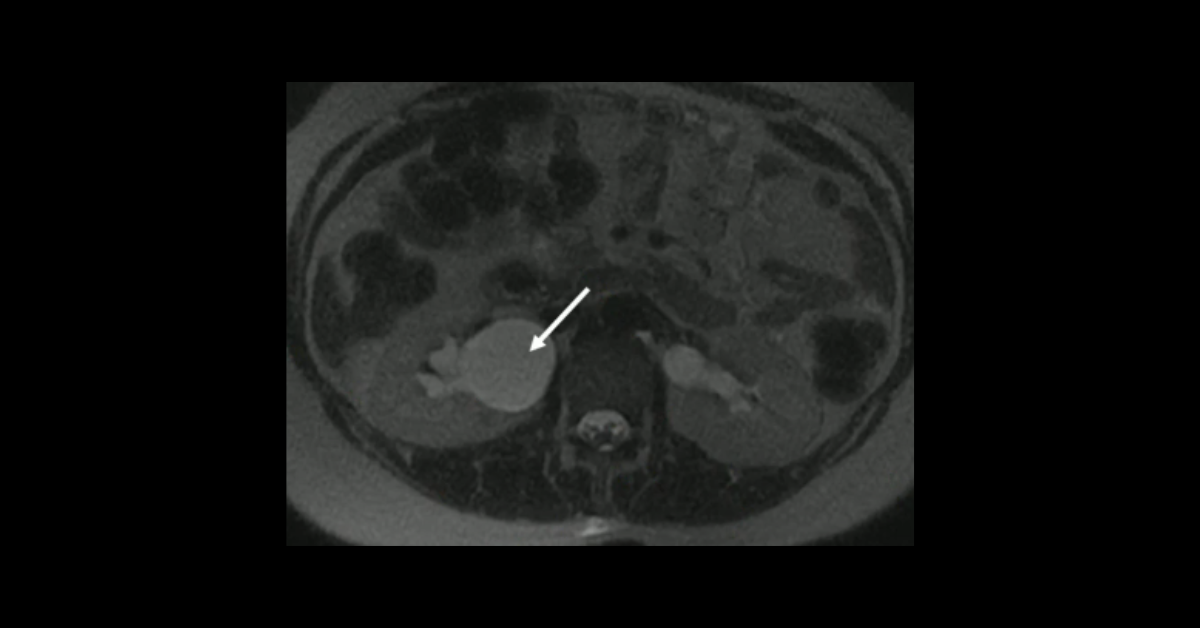

Presented by Ashish Khandelwal, MBBS, MD at Practical Radiology 2025. This talk will allow you to understand appropriate use of multimodal imaging in pregnant patient and know the imaging features of commonly encountered acute abdominopelvic conditions during pregnancy.

1. Understand appropriate use of multimodal imaging in pregnant patient

2. Know the imaging features of commonly encountered acute abdominopelvic conditions during pregnancy